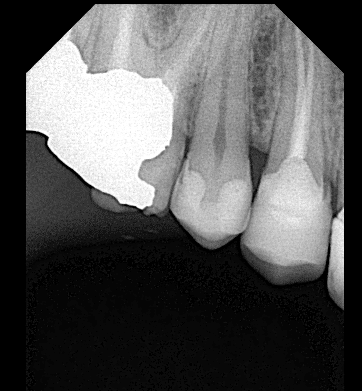

Pre-operative x ray showing the bad situation of the tooth